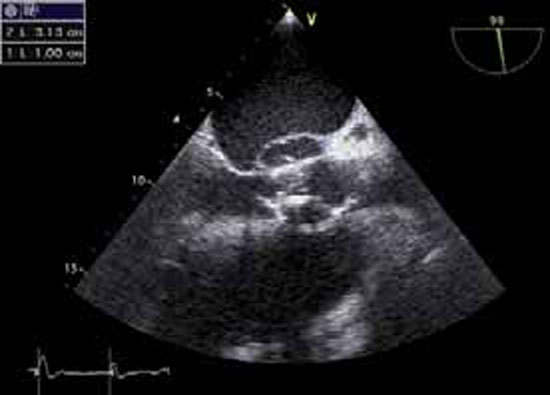

L’abcès péri-annulaire, sur valve native ou sur prothèse, est présent dans 30% des cas, visible le plus souvent en ETO et sur l’anneau aortique plutôt que mitral (figure 3).

Figure 3 : Abcès de l’anneau aortique postérieur (en haut de l’image en ETO)

Volumineux abcès détergé, de 31,3 mm x 10 mm sur bioprothèse aortique.